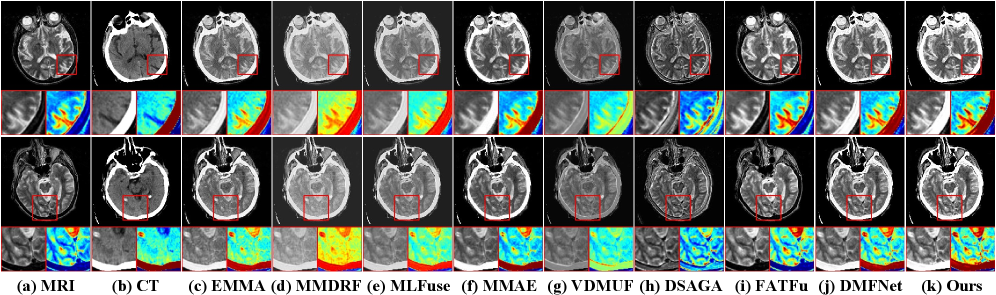

Qualitative Comparison. Figure 6 presents a visual comparison using two representative pairs of MRI and CT. CT images provide high-contrast information for bones and hard tissues, while MRI (T1, T2) reveals signal variations in soft tissues and lesion areas. EMMA and FATFusion lose crucial information from one modality, while MMDRFuse, MLFuse, and VDMUFusion produce images with low contrast, artifacts, or blurred lesion boundaries. DSAGAN introduces artifacts in some soft tissue areas, affecting lesion visibility. MMAE achieves good overall fusion quality, but the hierarchical sense in some soft tissue areas remains suboptimal. In contrast, our method, alongside DM-FNet, excels in generating sharp bone edges and smooth soft-tissue transitions, providing clearer diagnostic information.

Refer to caption

Figure 6: Visual comparison with eight SOTA methods in MRI-CT.

MRI functional image fusion (Figure 7) requires highlighting metabolic hotspots while preserving anatomical context. EMMA, MMDRFuse, and MMAE allow functional information to obscure anatomical details. VDMUFusion weakens metabolic information and causes severe texture loss. DSAGAN’s aggressive contrast enhancement introduces background artifacts. FATFusion preserves MRI structure but completely loses the high-intensity metabolic regions from the functional image. MLFuse also weakens some details. In contrast, our method and DM-FNet effectively integrate the functional tracer’s intensity and distribution into the precise MRI anatomical background, which is more conducive to accurate clinical diagnosis.

Figure 7: Visual comparison with eight SOTA methods in MRI-PET and MRI-SPECT.